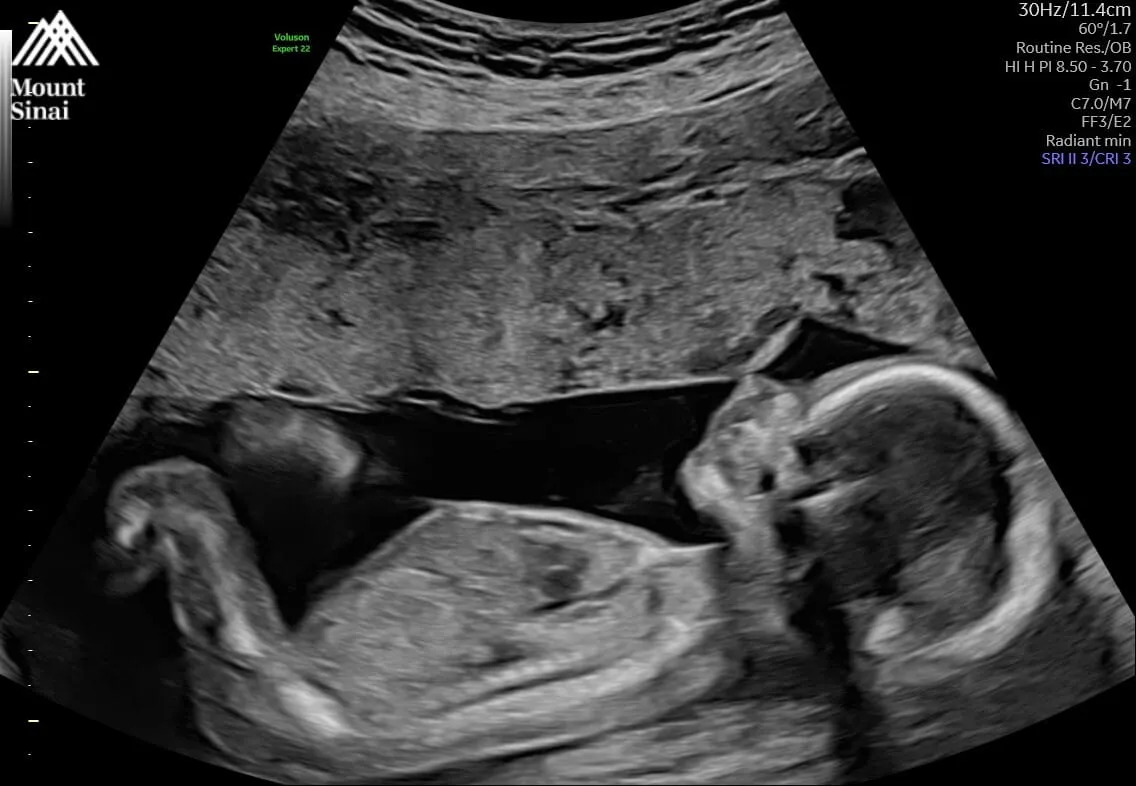

今广告小妹晒出宝宝的超音波照,透露「等了四年,助理回家了;等了三年,小聪回来了。谢谢大家的挂念,没发文的日子里,我一切都好。祝愿你们也好。」网友见状也纷纷留言恭喜,「太棒了,祝福一切平安顺利」、「哇,是小班长啊」、「恭喜,孩子是珍宝,眼眶泛泪」。